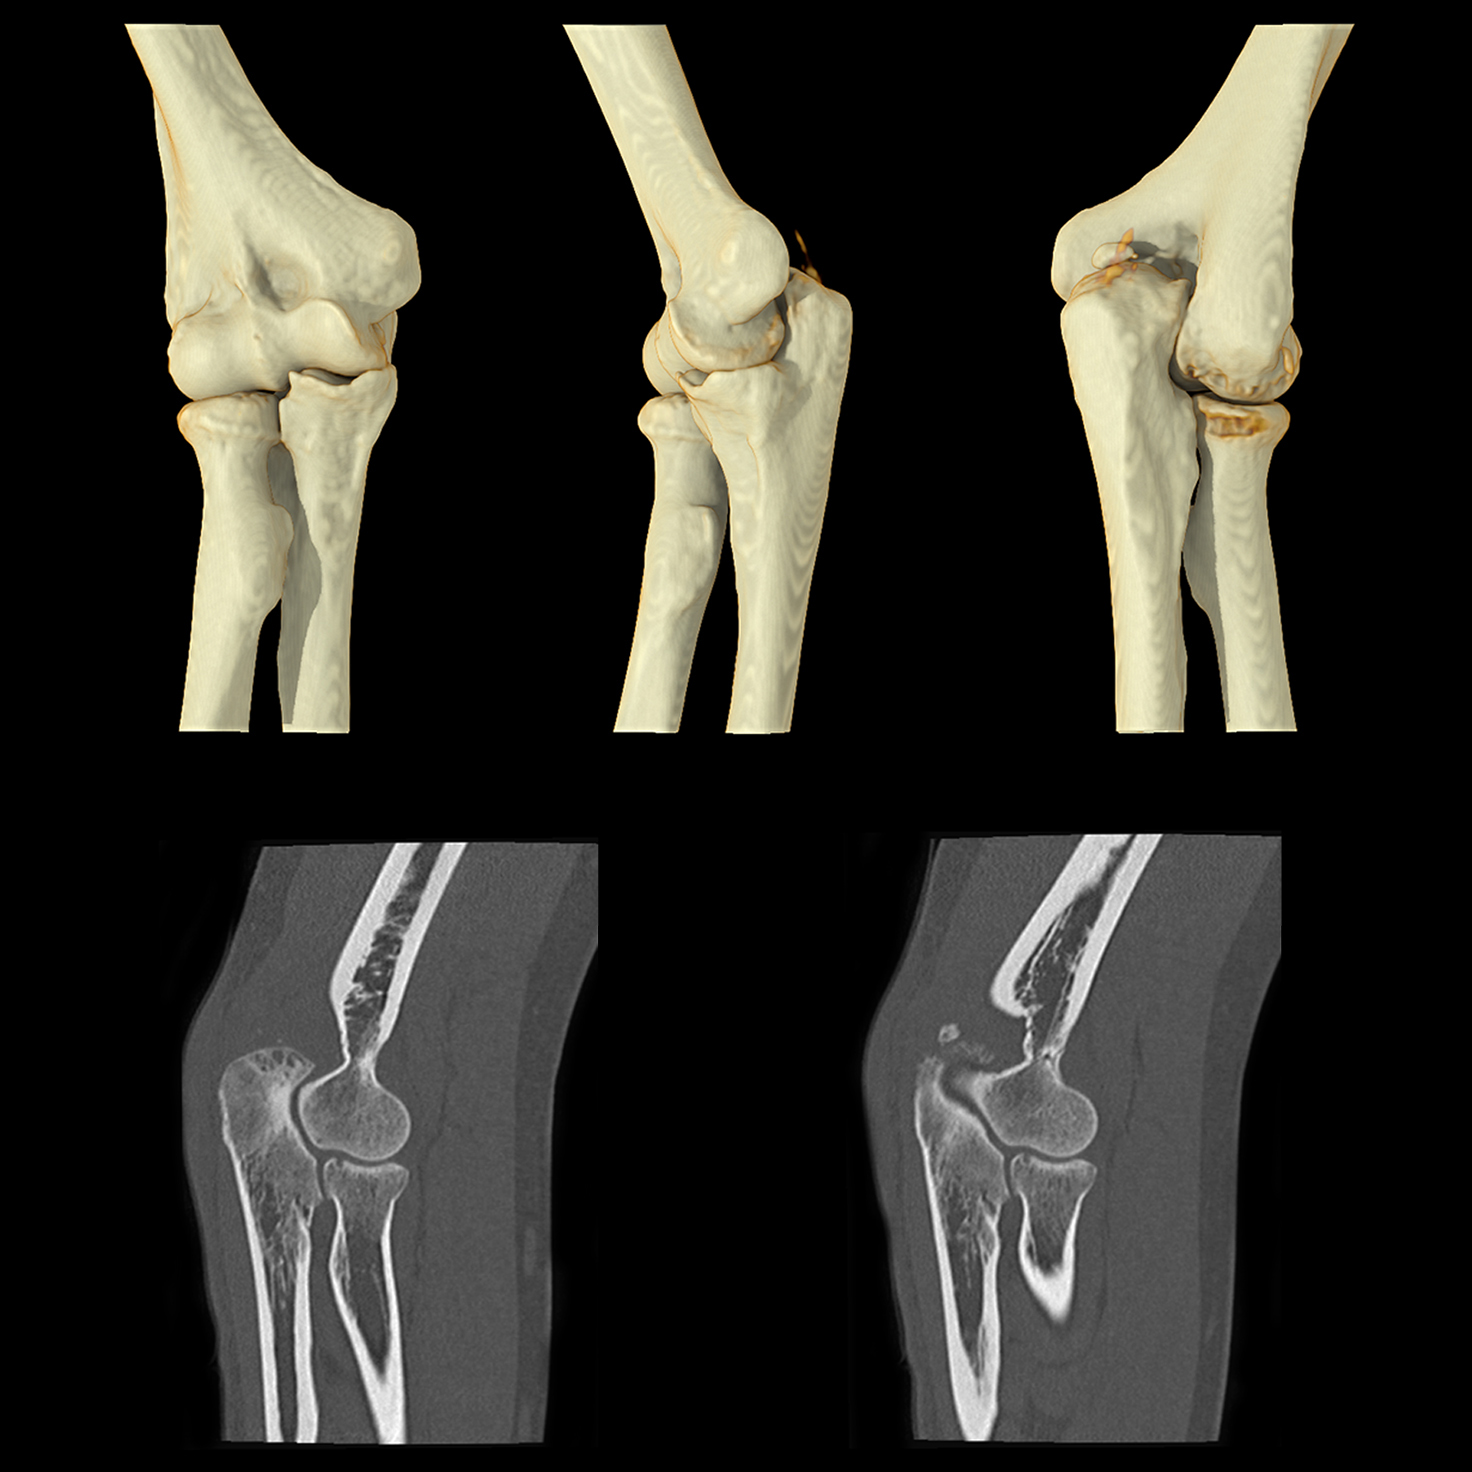

Технология реконструкции сверхвысокого разрешения для компьютерной томографии на основе глубокого обучения

Расширенный интеллектуальный модуль Clear-IQ Engine (AiCE)

КТ-реконструкция, в которой используются инновации глубокого обучения, чтобы соответствовать пространственному разрешению и малошумным свойствам усовершенствованных итеративных реконструкций на основе моделей для получения высококачественных изображений без ущерба для скорости или дозы.

- Малый шум

- Естественная текстура изображения

- Четкое высококонтрастное разрешение

- Четкая низкоконтрастная детектируемость